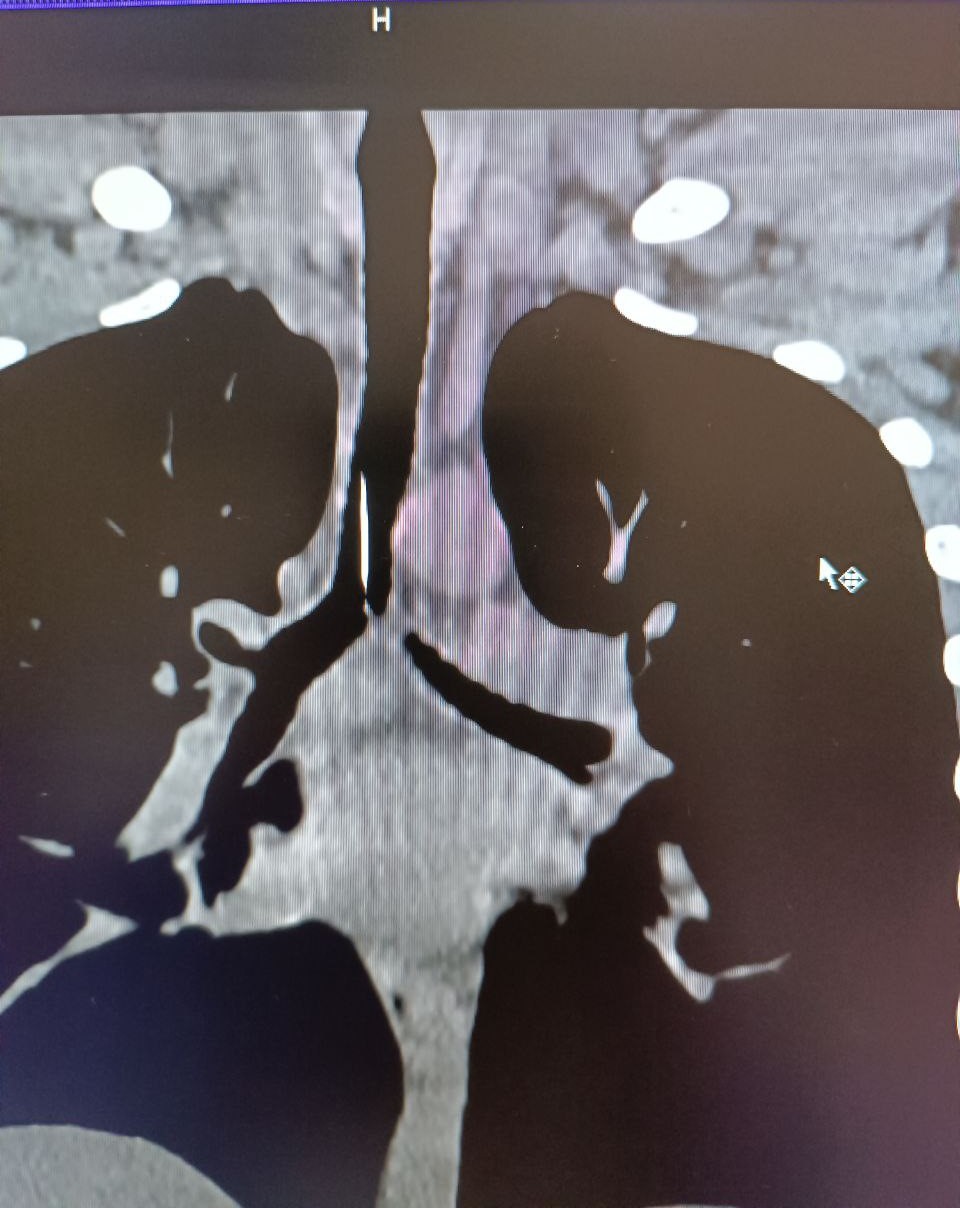

Клінічний випадок трапився 2 лютого. Підліток був доставлений до приймального відділення міської лікарні з одного з селищ району зі стороннім тілом в трахеї.

Завдяки високій кваліфікації чергового хірурга та анестезіологічної бригади, ендоскопічним методом було видалено стороннє тіло - голка довжиною 4 см.

Підлітку під наркозом провели бронхоскопію та дістали шпильку, яка гострим кінцем встромилася у слизову та нікуди не рухалася.

Гострий предмет міг викликати перфорацію - пробити легені або через стінку бронха потрапити і в серце. Наслідки могли бути трагічними.